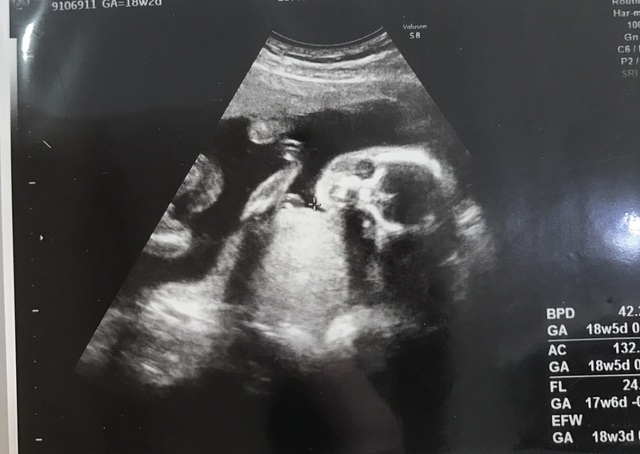

18週1日(18w1d・性別不明)|たんたか さん(40歳)

エコー写真撮影時のエピソード:

子どもが手を挙げてるようにみえてうれしく思い それと同時に神秘的だなーって夫婦で思ってました 早く赤ちゃんに会いたいなぁ

今度は4Dで診るよていなので楽しみです ワクワク その時に性別がわかるといいなぁ(о´∀`о)